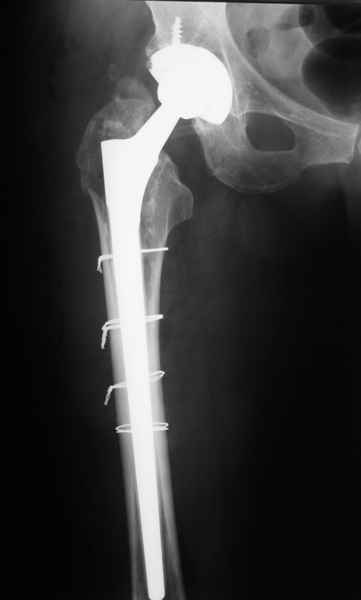

2. Применение ножки дистальной фиксации, мы отдаем предпочтение ножке Вагнера с фиксацией проксимального отдела на ножке. Более травматичное вмешательство, но при стабильной фиксации ножки реабилитация идет в обычном режиме.

Хочется показать два подобных случая, П-ка Зубарева 72 лет и п-т Гладковский 80 лет. Сразу принимаю замечание, что это были ножки цементной фиксации, просто под руками не было бесцементника.